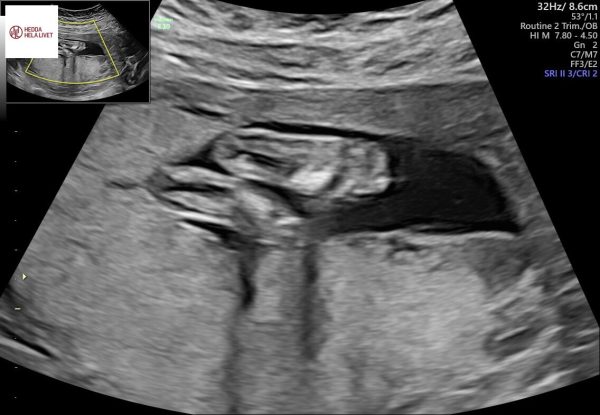

Idag var det dags för det traditionella rutinultraljudet som sannolikt också är det sista ultraljudet som kommer att göras. Det var Ida, jag och en till vän som var med. Allt såg bra ut och lilla flickan sög på tummen och vinkade till Idas vän ❤️